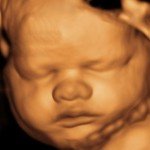

4D/5D/HD Ultrasound Gallery

Gallery